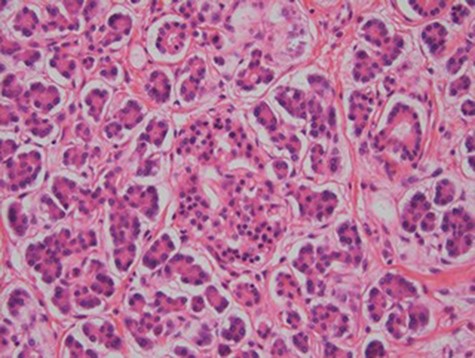

At laparoscopy, there were very dilated and inflamed loops of small bowel, and the appendix appeared normal macroscopically. Due to the extent of bowel dilatation obscuring adequate laparoscopic vision and assessment, decision was made to convert to an open procedure. At laparotomy, there was a nodular mass in the jejunal mesentery measuring about 3 cm in diameter with central necrotic tissue (Fig. 1). As it was adherent to the surrounding bowel, a limited small bowel resection was performed (Fig. 2) with side to side stapled anastomosis. Histology revealed normal small bowel wall with a mesenteric nodular mass comprised of architecturally normal pancreatic tissue including exocrine ducts and endocrine islets of Langerhans (Figs 3–5), consistent with a diagnosis of mesenteric heterotopic pancreas. His post-surgical recovery was uneventful and was discharged after five days of stay in hospital. He had an outpatient magnetic resonance imaging (MRI) of the pancreas which reviewed normal pancreas tissue, and he was followed up three months post-surgery.

Our patient had type 1 heterotopic pancreas, which is the most common type.